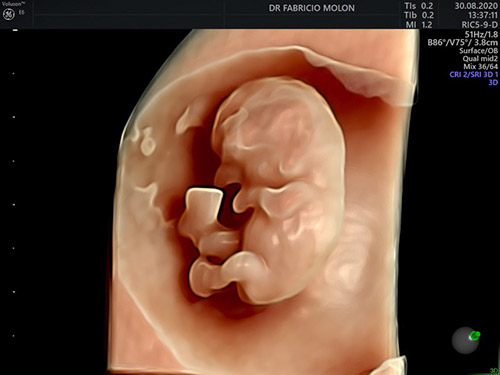

US 3D/4D e 5D com HD live

É possível conhecer o rostinho do bebê ainda na barriga, com a ultrassonografia 4D e 5D! Essa tecnologia permite ver a face do bebê com uma precisão incrível, além de poder gravar as imagens.

O exame traz melhores imagens quando realizado entre 26 e 30 semanas.